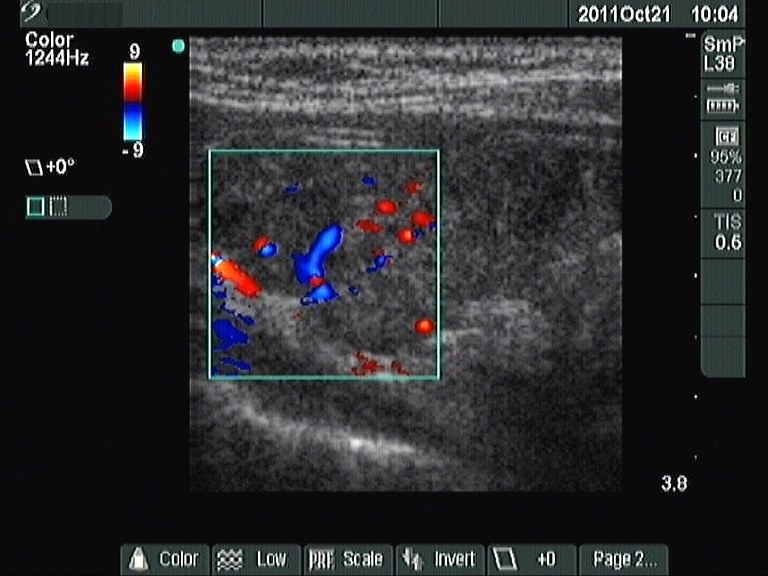

First examination (1st row of images):

Ultrasonography: revealed hypoechogenic inhomogeneous thyroids. There was a hyperechogenic nodule in the left lobe. The nodule presented a halo sign and perinodular blood flow. It increased in size, therefore we performed aspiration cytology.Cytology: benign lesion.

Most solitary nodules which are greater than 2 cm in maximal diameter, display a halo sign and perinodular blood flow are proved to be follicular tumor. This case belongs to the relatively rare exceptions.